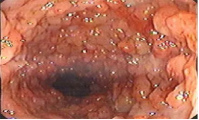

肛窦炎◈✿✿,这一听起来或许有些陌生的疾病K8凯发马竞赞助商◈✿✿,实则在我们的日常生活中并不少见◈✿✿。它又称肛隐窝炎◈✿✿,是肛门齿线部的肛隐窝发生的炎症

炎症刺激和黏膜分泌物的改变可能导致肛门周围出现瘙痒感6喝彩◈✿✿,同时◈✿✿,局部组织充血和水肿也会使患者感觉肛门区域肿胀K8凯发马竞赞助商◈✿✿。

②引发肛门疾病肛窦炎常为肛门周围脓肿K8凯发马竞赞助商K8凯发马竞赞助商◈✿✿、肛瘘等的前驱表现◈✿✿,如未能及时治疗◈✿✿,易导致后者的发生k8凯发携手马竞◈✿✿,◈✿✿,产生肛门周围反复红肿◈✿✿、疼痛◈✿✿、化脓等6喝彩◈✿✿。